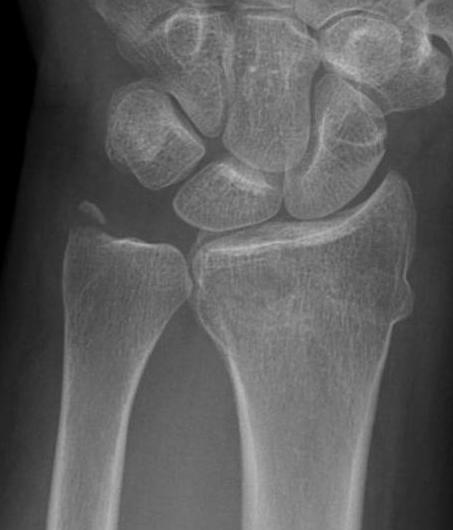

Xray

True lateral

- radial styloid overlies proximal scaphoid / lunate / triquetram

Dorsal subluxation of the distal ulna

CT